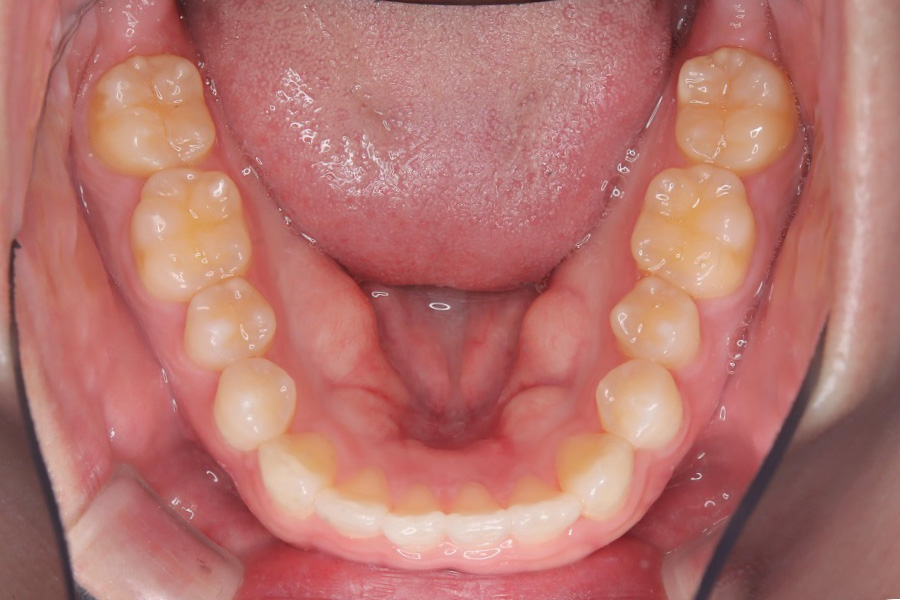

治療後

主訴 歯のガタつき

期間 1年半

治療内容 インビザライン矯正

非抜歯